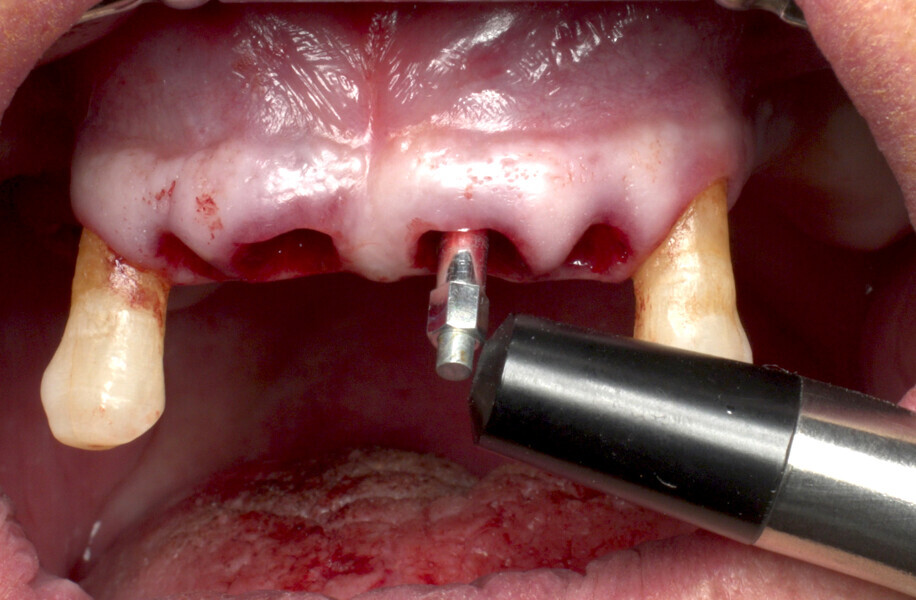

The fully digital Pro Arch protocol